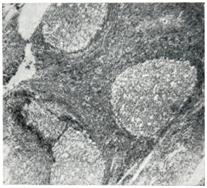

Длительное хроническое воспаление гиперплазированной глоточной миндалины (рис. 1 и 2) ведет к ее склерозированию, но с сохранением значительных участков с воспалительными инфильтратами.